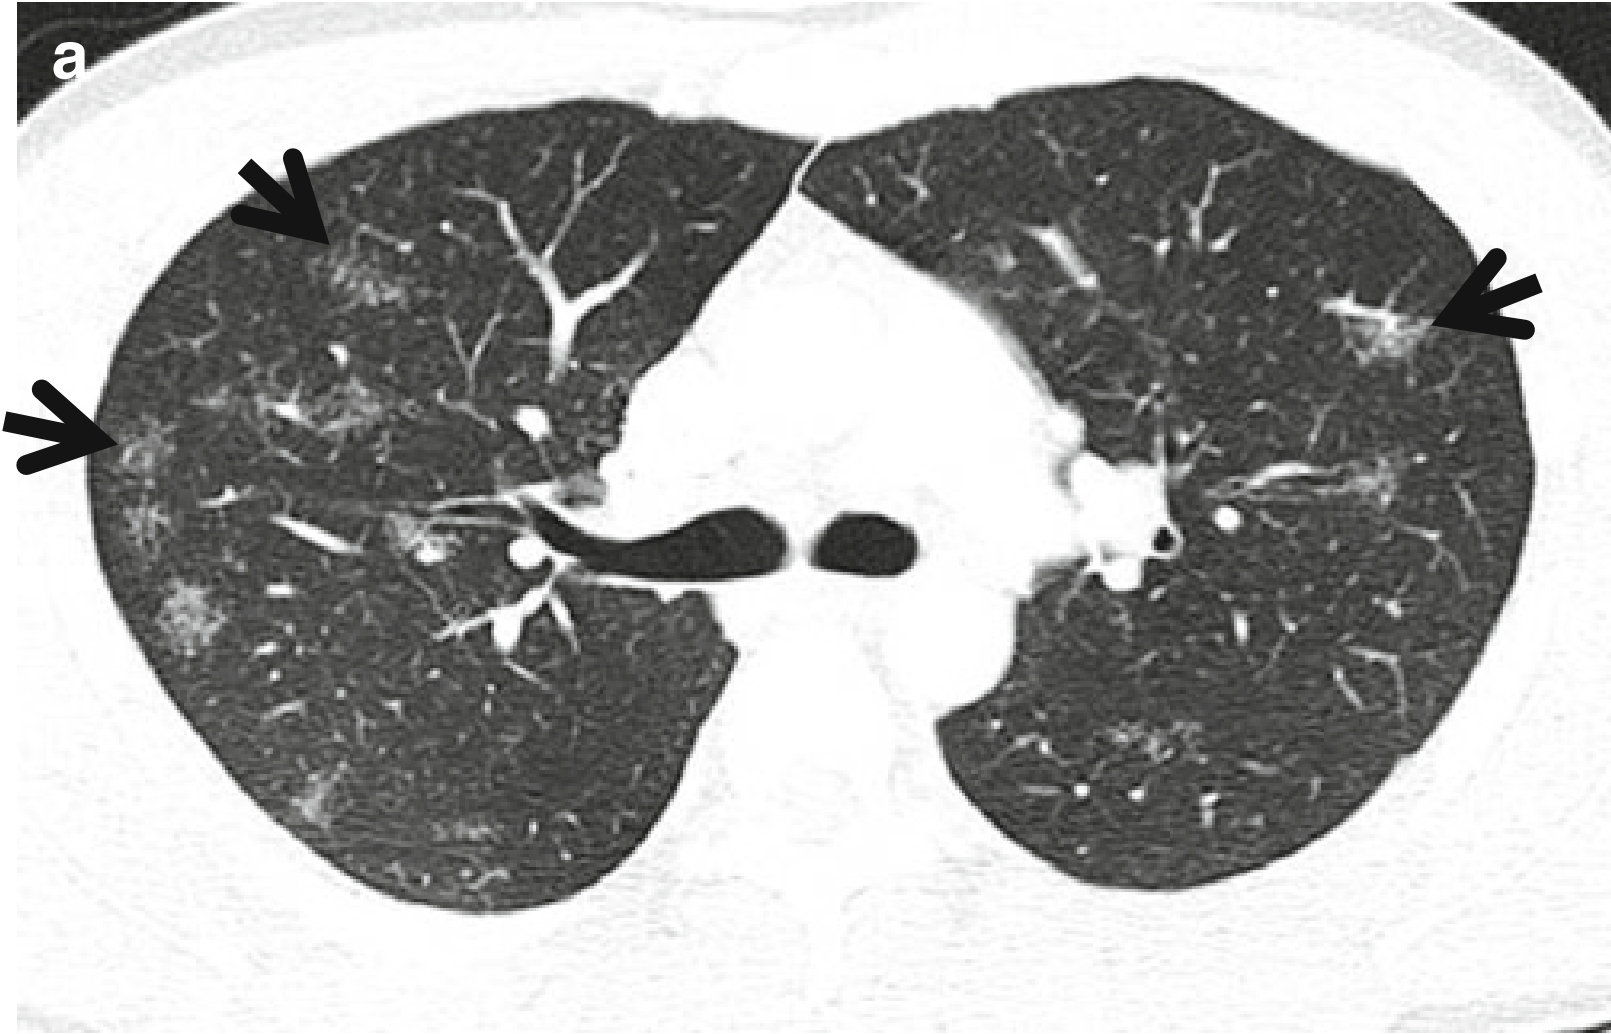

图3 CT星系征。男,53岁,活动性肺结核患者。薄层CT扫描(层厚=2.5mm)分别于主动脉弓水平(a)和奇静脉弓(b)水平肺窗示双肺上叶和左肺下叶背段的星系征(箭头所示)。